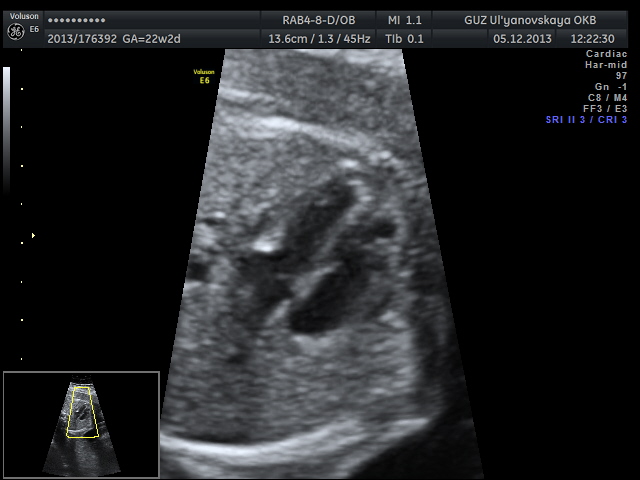

Дальше сердечко....